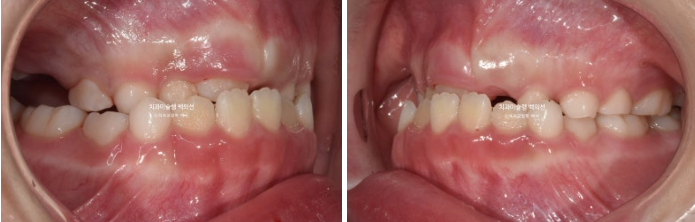

2022년 8월 내원한 어린이 입니다.

앞니 반대교합과 비대칭 치료를 위해 오셨습니다.

앞니 뿐 아니라 송곳니, 일부 어금니까지 거꾸로 물리는 상황입니다.

앞니 반대교합은 프리올소와 같은 장치로 간단하게 넘겨줄 수 있지만 더 큰 문제는 비대칭입니다.

아래앞니와 함께 아래턱이 우측으로 돌아가 있습니다.